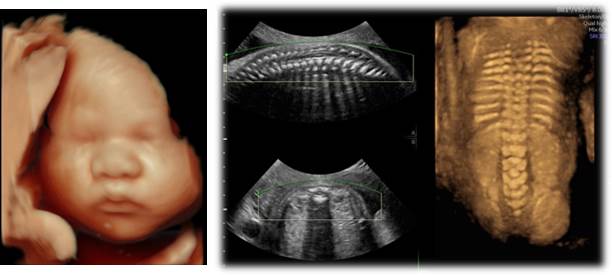

태아 정밀 초음파 클리닉은 임신부의 복부를 통하여 태아 이상을 진단하며 태아 머리부터 발끝까지 중추신경계, 근골격계, 순환기계, 비뇨생식기계 등을 세밀하게 관찰하고 주요 장기의 선천성 기형을 평가합니다.

정밀 초음파는 임신 1분기 뇌신경초음파와 2분기 정밀초음파로 나뉘는데, 고위험 임산부 및 이전에 기형 태아 임신이나 분만 경험이 있는 산모에 대해 태아의 신체적 구조를 면밀하게 평가하기 위해 시행합니다.

초음파 검사는 검사자의 숙련도가 초음파의 정확도와 밀접한 관련이 있습니다. 태아 정밀 초음파 클리닉에서는 대한 산부인과 초음파학회의 연수를 수료한 전문 산과 의료진이 초음파 검사를 직접 시행함으로써 보다 정확한 진단을 하고 있습니다.